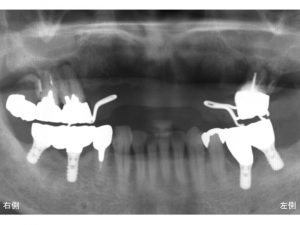

以下が先日行ったインプラント手術直後のレントゲンです。

これから約2ヶ月後に被せ物が装着され、噛めるようになります。